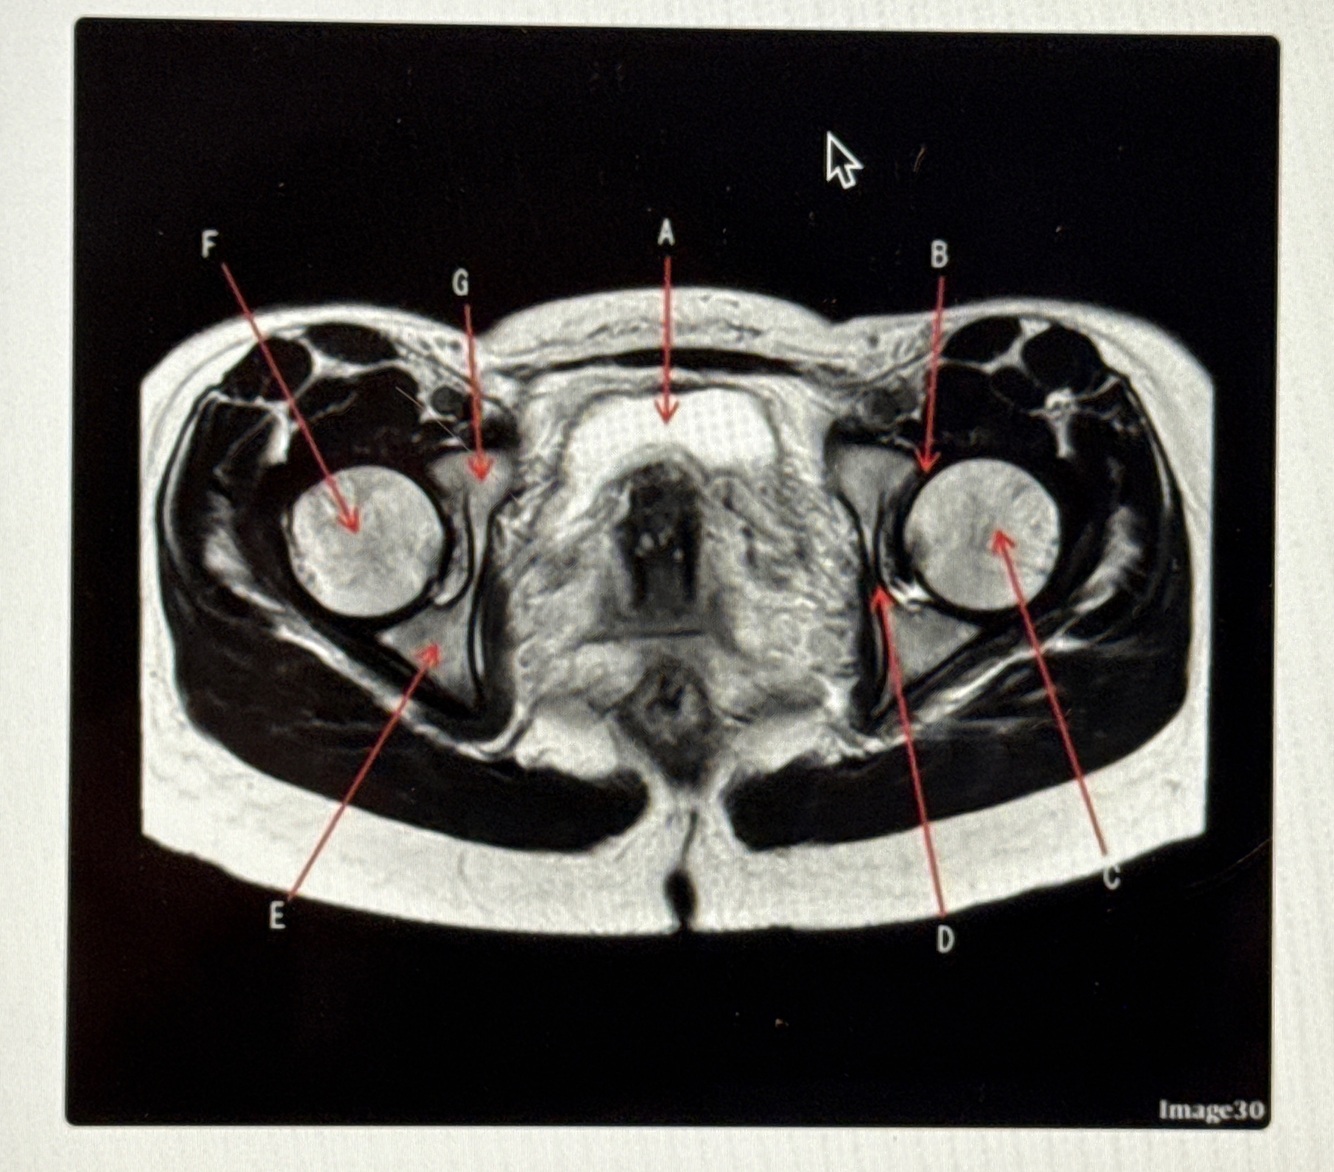

The image below is a ______ weighted image acquired in the _____ scan plane.

T2; Axial

Letter A is pointing to the

Bladder

Letter B is pointing to the

Labrum

Letter C points to the

Femoral neck

Letter D points to the

Obturator externus

Letter E points to the

Adductor muscles

Letter F points to the

Vastus lateralis

Letter G points to the

Femur